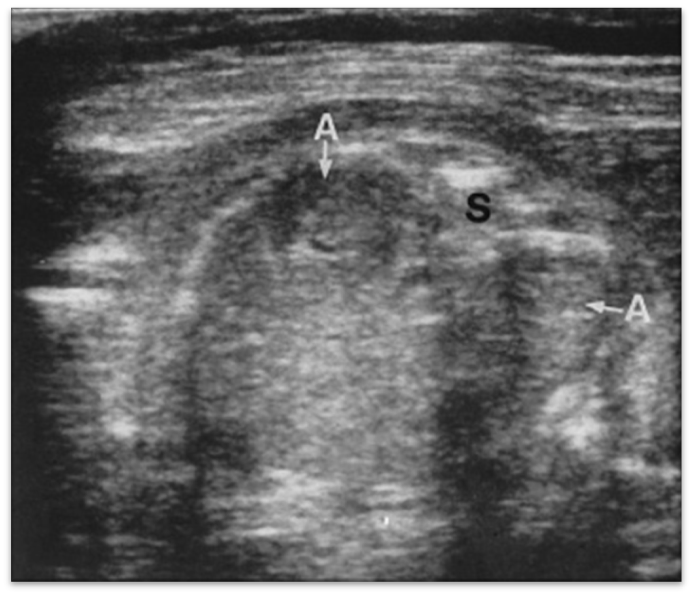

enlarged adrenal glands

renal agenesis